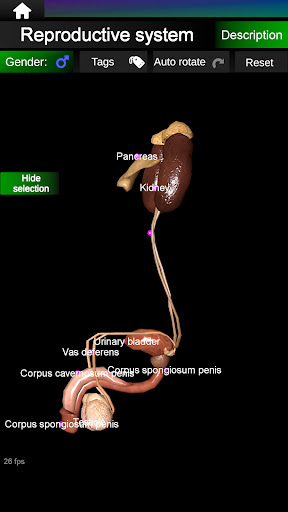

* Reproductive system, which includes the male and female reproductive organs.

Shows a 3D anatomical model of the main organs of the human body and a description of each one.

* Easy to access and navigate (zoom, 3D rotation).

* Hide or show information.

* Compare male and female organs.

* Descriptions of each organ.